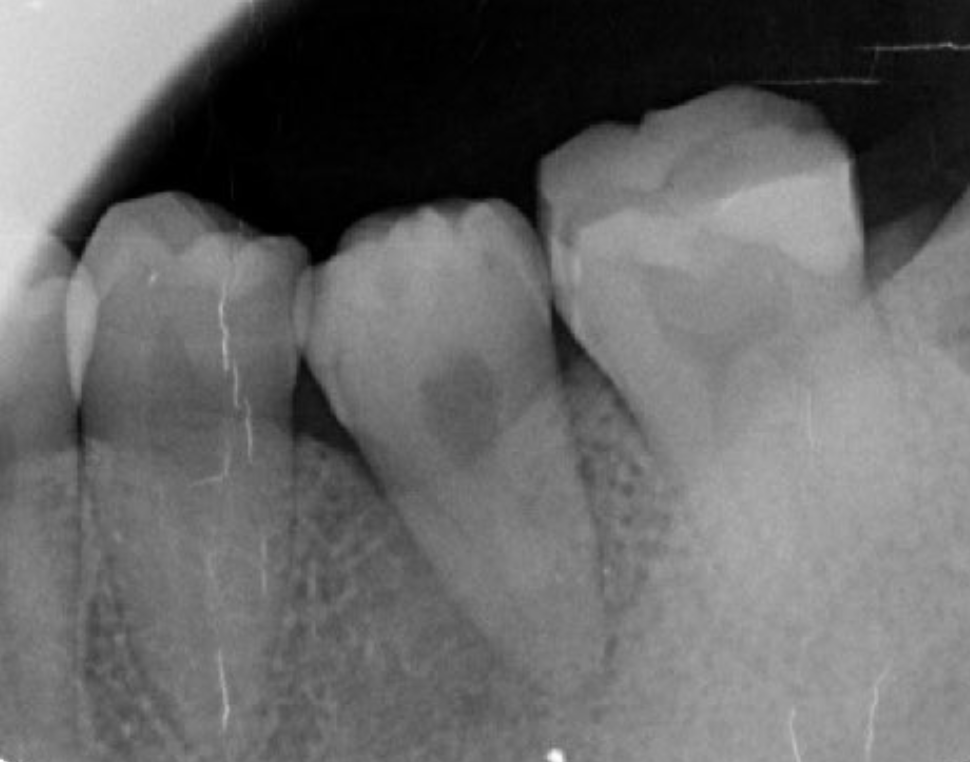

Figure 2.Pre-treatment X-ray findings. A cystic lesion was found in the mesial and distal roots apex, and root nodule of #46.